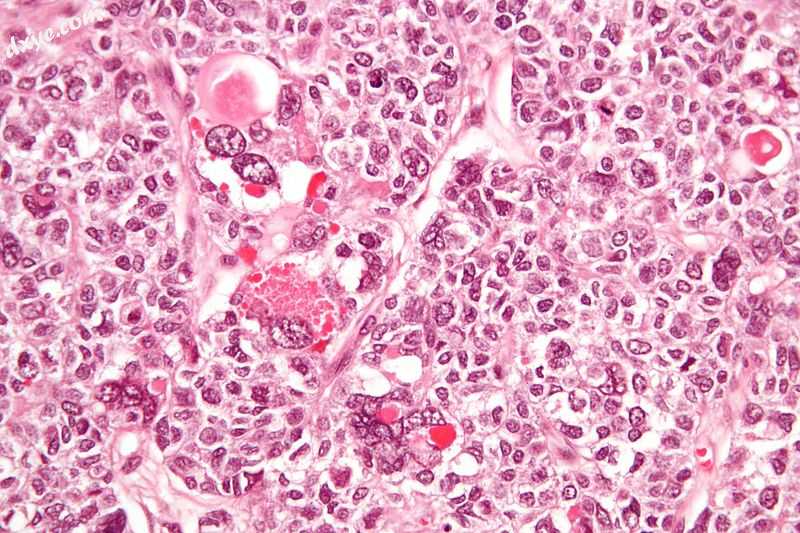

Micrograph of a juvenile 卵巢颗粒细胞瘤 with hyaline g耳垂s. H&E stain..jpg

带有透明性小球的卵巢颗粒细胞瘤的显微照片。 H&E污渍。